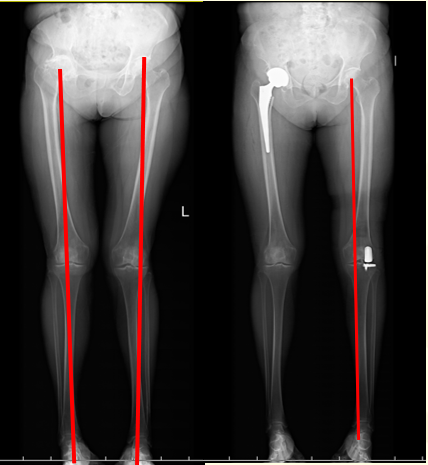

赖阿姨,65岁。30年前右髋关节结核做了手术,后面遗留畸形,不能行走,渐渐的继发了左膝关节疼痛,表现为膝关节外侧疼痛,外翻畸形。考虑到她还很年轻,治疗方式为:同时做了右侧人工髋关节置换术和左侧膝关节外侧单髁置换术,术后恢复顺利,1个月已经可以正常行走

还有约10%的膝骨关节炎会累及到膝关节外侧的软骨,表现出膝关节外侧疼痛,外翻畸形等。同样,我们可以根据患者的要求、疼痛的程度、软骨退化的情况等,选择截骨手术和膝关节外侧单髁置换术,手术技术成熟,可以取得良好的治疗效果。

在选择治疗方式前,我们首先需要照双下肢全长负重位正侧位X线片和髌骨30°轴位X线片,可以判断是关节内畸形还是关节外畸形;必要时加照膝关节内翻或者外翻应力位正位照片,查明是膝关节内侧或者外侧软骨退变的轻重和部位。膝关节磁共振检查对于诊断半月板退变、撕裂和脱位及评估软骨的厚度方面具有一定的价值。